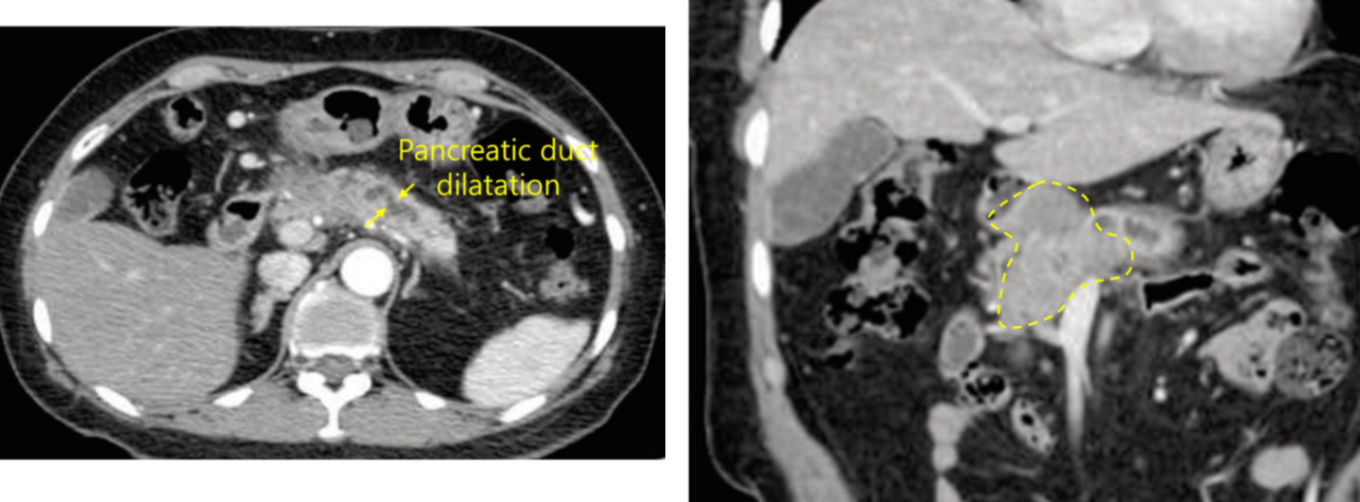

60세 여자가 건강검진 복부 초음파검사에서 배에서 덩이가 발견되었다며 병원에 왔다. 평소 건강하였으며 특이 과거력은 없다. 혈압 104/74 mmHg, 맥박 78회/분, 호흡 20회/분, 체온 36.4℃이다. 복부 신체진찰에서 특이소견은 없다. 혈액검사 결과는 다음과 같다. 복부 컴퓨터단층촬영 사진이다. 진단은?

Img | CT: Pancreatic head and body mass, pancreatic ductal dilatation |

CA 19-9 elevation이 저명하며 CT상 pancreatic mass가 있으므로 pancreatic cancer가 가장 가능성 높은 진단명이다.

• CT상 pancreatic head 및 body에 mass가 확인된다. 높은 CA 19-9 수치와 종합하면 pancreatic cancer의 가능성이 가장 높다.

진단 | • CT: Pancreatic mass, pancreatic duct dilatation(head cancer의 경우) • MRCP: Double-duct sign(head cancer의 경우) |